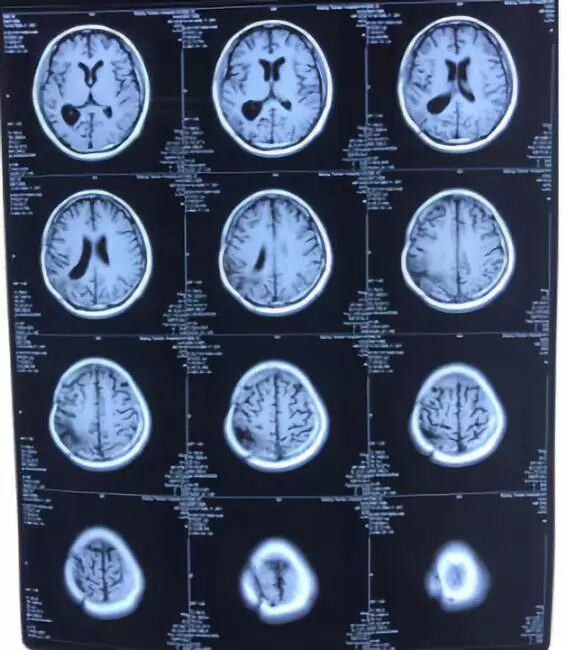

第二次手术后两个月,患者于2017年05月27日于湘雅医院行颅脑MRI复查(图7)未发现明显肿瘤复发迹象,考虑第一次术后肿瘤短期复发,建议患者行基因检测,于北京泛生子基因科技有限公司进行了脑肿瘤68基因和6项基因检测,结果示患者IDH及TERT基因无突变,且MGMT无甲基化,提示患者对化疗抵抗(图8); 然而,检测发现患者存在BRAF-V600E突变,这一重要发现提示患者服用靶向药维莫非尼可获益,遂前往北京天坛医院复发胶质瘤MDT门诊行靶向治疗(图9)。

2017年6月4日,对患者保肝治疗两天后进入天坛医院血液肿瘤科进行维莫非尼治疗,用药6天半皮疹严重,停药5天后继续用药,用药一个周期后,复查(图10)MRI示病情得以控制,继续6个周期替莫唑胺辅助化疗(图11),持续动态观察(图12,13,14),直至最近于2018年12月08日于湘雅医院复查(图15),病情无进展,患者神清,自主活动,一般情况良好,母子生活质量理想。

图12. 维莫非尼治疗后复查(2017.12.14)

图13. 维莫非尼治疗后复查(2018.03.20)

图14. 维莫非尼治疗后复查(2018.06.09)

图15. 最近复查结果(2018.12.08)